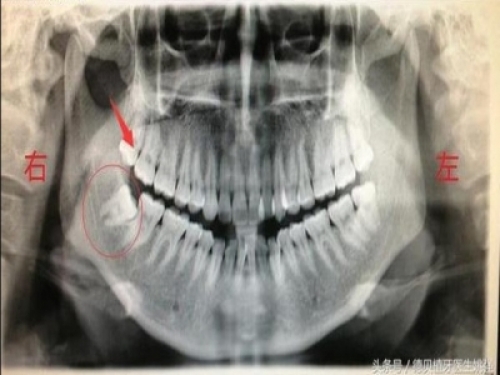

2、侵略鄰牙:一般患者不自知,而由牙醫以X光確診得知。一般智齒萌生的空間缺乏,而會倒在第二大臼齒上,因而構成第二大臼齒清洗不易,乃至是牙齒有些吸收的表象,構成患者不舒服或牙疼。

5、阻生齒:一般這是最厭煩的一種,牙醫會覺得很難搞定,但患者卻不一定有感受,因而疏忽了。這一種型別的牙齒,一般埋在齒槽骨的裡邊,假如會痛,或是確診會有病灶發作的時分,就需求拔除了。